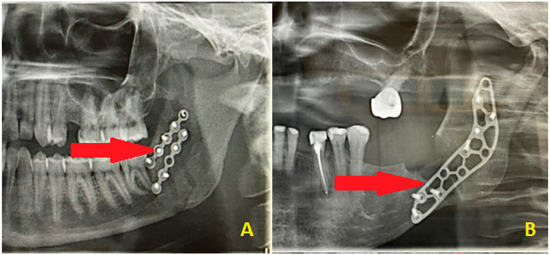

Pathological Fractures of the Mandible: Our Department’s 15-Year Experience

Background/Objectives: Pathological fractures of the mandible are uncommon and often result from underlying conditions such as osteoradionecrosis, malignancies, or medication-related osteonecrosis of the jaw (MRONJ). Their management is challenging due to compromised bone quality and complex patient comorbidities. This study presents a [...] Read more.

Background/Objectives: Pathological fractures of the mandible are uncommon and often result from underlying conditions such as osteoradionecrosis, malignancies, or medication-related osteonecrosis of the jaw (MRONJ). Their management is challenging due to compromised bone quality and complex patient comorbidities. This study presents a 15-year experience from a tertiary oral and maxillofacial surgery center, highlighting the clinical characteristics, etiologies, treatment approaches, and outcomes of these fractures. Methods: A retrospective review was conducted on patients diagnosed with pathological mandibular fractures between 2010 and 2024. Data collected included demographics, fracture etiology and location, diagnostic imaging, treatment modality, complications, and long-term outcomes. Results: Fifty patients met the inclusion criteria. The mean age was 66.4 years, with a predominance of male patients (78%). The most common etiology was osteoradionecrosis (48%), followed by primary malignancy (22%) and MRONJ (16%). In 82% of cases, surgical management was required, most frequently involving marginal or segmental mandibular resection (gnathectomy), with or without immediate reconstruction. Conservative treatment was reserved for select cases with high surgical risk. Complications occurred in 54% of patients, including persistent fistulas, pathological communication with the skin or oral cavity, and the need for revision surgery. Long-term follow-up revealed variable survival, with many patients experiencing reduced quality of life due to complex postoperative courses. Conclusions: Pathological fractures of the mandible present significant diagnostic and therapeutic challenges, particularly in patients with osteoradionecrosis or malignancies. Early diagnosis and individualized, multidisciplinary treatment planning are essential. This study underscores the need for a standardized classification system and treatment algorithm to guide management and improve outcomes in this complex patient population. Full article

Figure 1